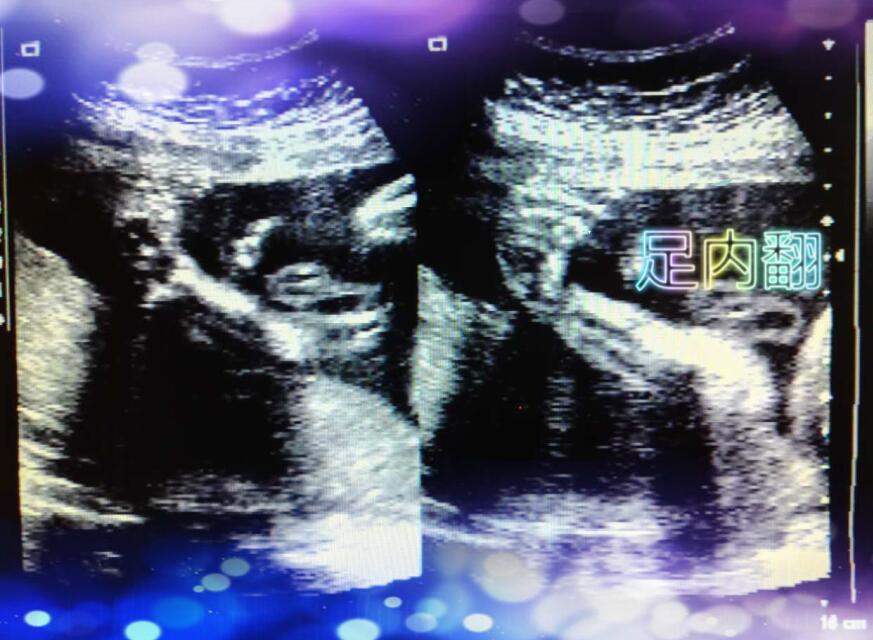

我院超声室诊断胎儿足内翻一例

患者罗女士,40岁,高龄孕妇,来我院行超声检查。针对其特殊性,超声室按照会诊制度,由高年资大夫组织技术骨干为其进行检查。经检查发现胎儿双足曲度异常,遂嘱其一小时后复查;再次观察后,未见明显改变:双足向内弯曲,呈”镰刀形“,拟诊断为胎儿双足内翻。随后,在上级医院确诊。

此病可以经产前超声诊断,在孕中期进行检查较为可靠,这时胎儿大小适中,羊水量相对较多,胎儿活动空间大,四肢较易显示,有利于辨别胎儿肢体形态;局部羊水过少、孕周较大可造成胎儿的脚被子宫壁和胎盘压迫,影响判断。此例正值妊娠中期,因而较易显示足部形态结构。